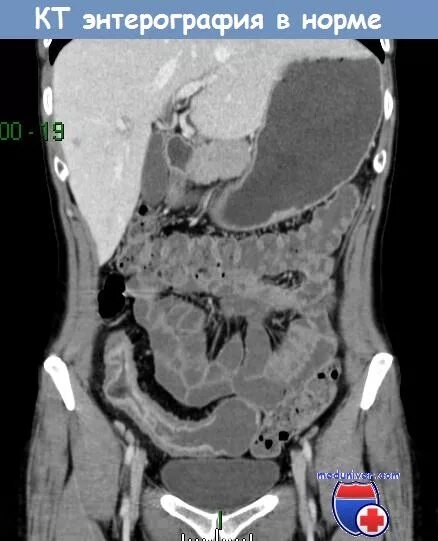

Энтерография сделать